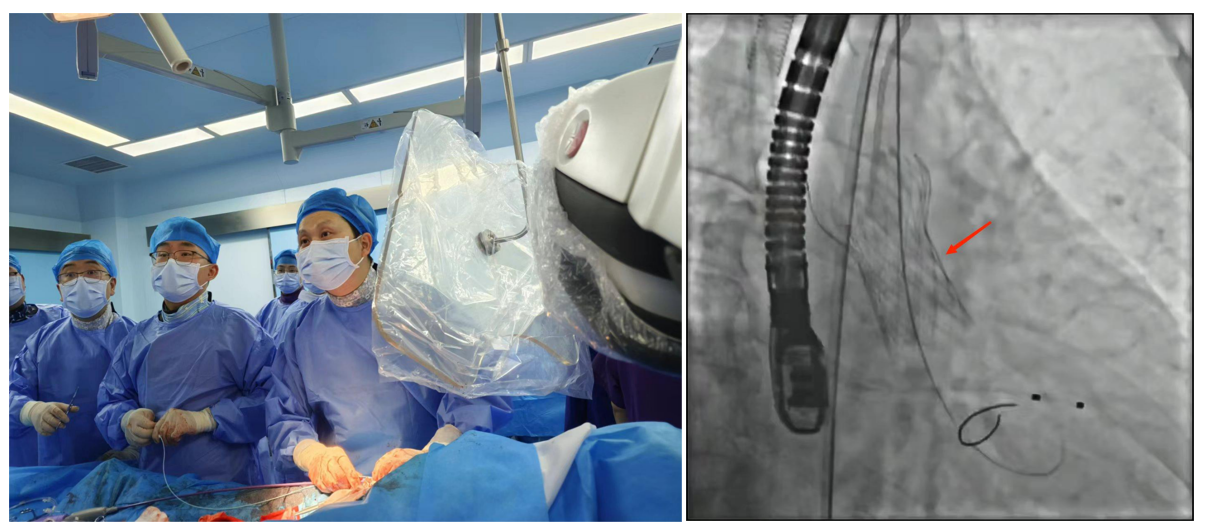

2.經(jīng)導(dǎo)管主動(dòng)脈瓣置入術(shù)(TAVI)通過股動(dòng)脈送入介入導(dǎo)管,將人工心臟瓣膜輸送至主動(dòng)脈瓣區(qū)打開,從而完成人工瓣膜置入,恢復(fù)瓣膜功能。手術(shù)無需開胸,因而創(chuàng)傷小、術(shù)后恢復(fù)快。

8620ab9f9f5343229c6d31c5723ea8ca.Png

經(jīng)導(dǎo)管主動(dòng)脈瓣置入術(shù)(TAVI)